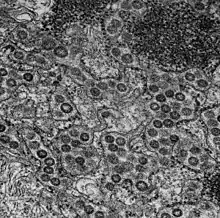

MRC-5 (Medical Research Council cell strain 5) is a diploid cell culture line composed of fibroblasts, originally developed from the lung tissue of a 14-week-old aborted Caucasian male fetus.[1][2] The cell line was isolated by J.P. Jacobs and colleagues in September 1966 from the seventh population doubling of the original strain, and MRC-5 cells themselves are known to reach senescence in around 45 population doublings.[2][3][4]